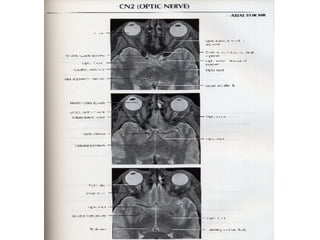

Nervos Cranianos Nervo Optico- II Par 􀂄  Sensitivo 􀂄  Aferente somático especial

Nervos Cranianos NervoOptico- II Par 􀂄 Sensitivo 􀂄 Aferente somático especial